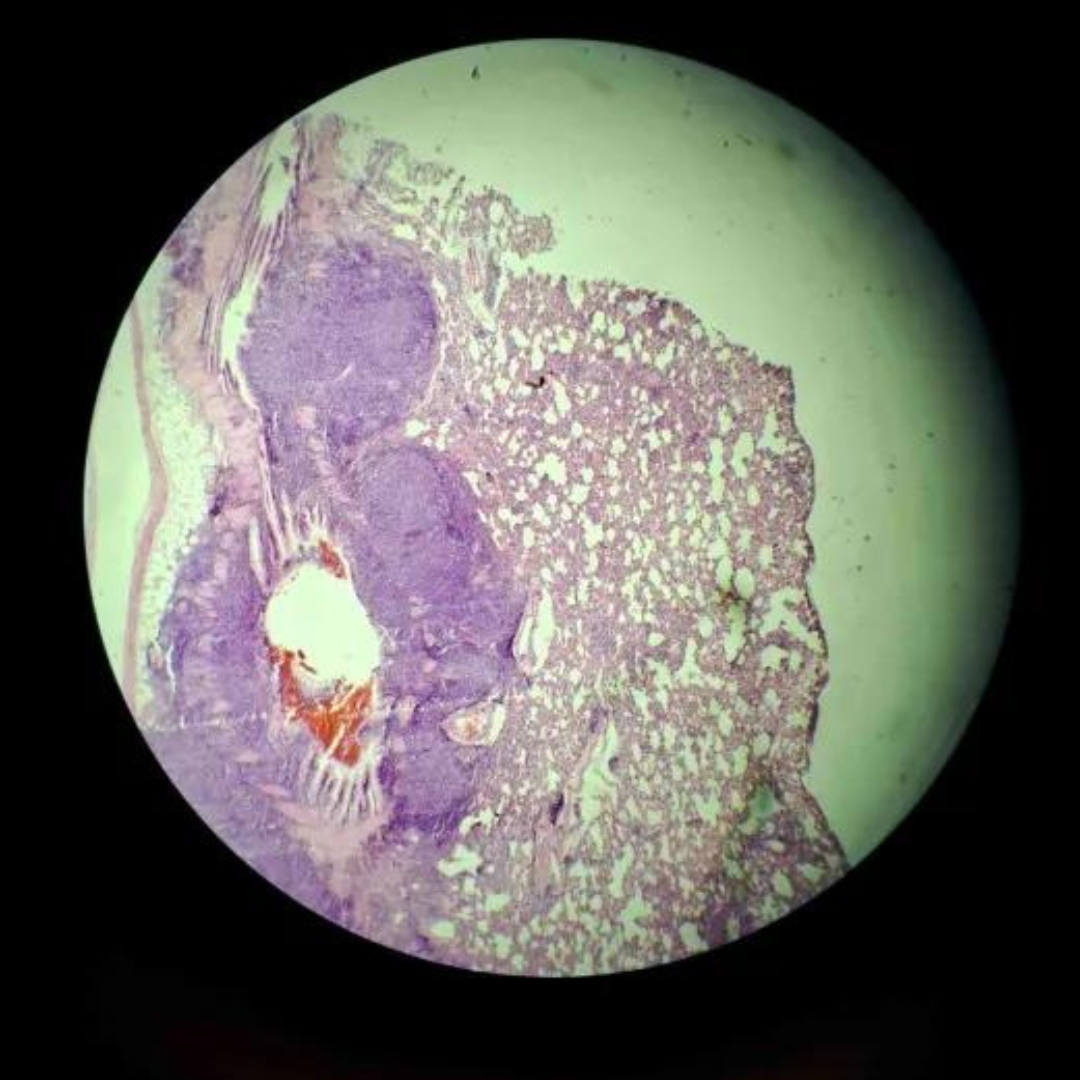

Bronchi

Bronchi

Bronchi

Bronchi